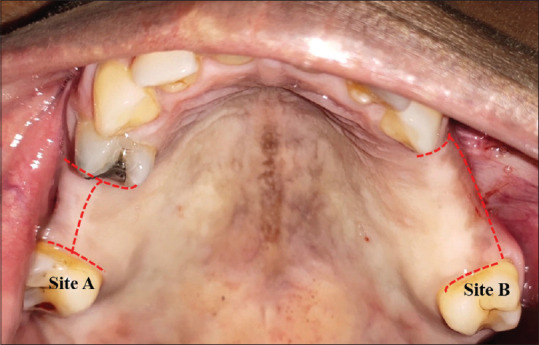

Materials and methods: A clinical study was conducted at the department of implantology with a total number of 30 patients. Patients with bilateral edentulous sites for whom dental implant placement was planned were included in the study. Mid-crestal incision design on one side and subcrestal incision design on other side were performed. Healing was evaluated at 1- and 4-week intervals postoperatively using an early wound healing score (EHS). The pain perception from the patient was also noted after 1 week on the day of suture removal using Visual Analogue Scale (VAS) values ranging from 0 to 10.